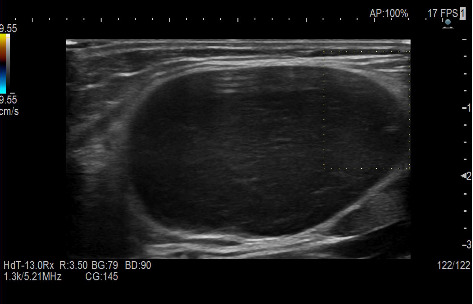

Hodgkin lymphoma (HL) is a type of lymphoma, characterized by the presence of abnormal Reed-Sternberg cells. It typically affects lymph nodes, generally in the upper body (such as neck, chest, and armpits). It can also involve the spleen, liver, and bone marrow. In the literature, there are sporadic cases of atypical localization of HL. The aim of this article is to report a peculiar case of HL in a 55-year-old male presenting with primary epitrochlear lymphadenopathy as the only localization of disease, also performing a literature review on this atypical presentation. We also summarized the possible underlying malignant pathologies that arise from the soft tissues of the upper limb adjacent to the elbow.